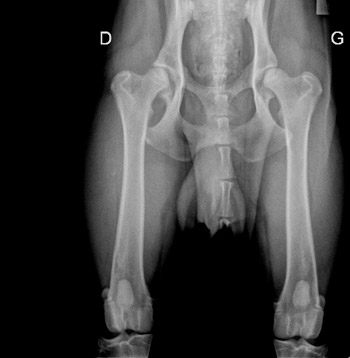

La dysplasie de la hanche (HD)

La dysplasie est un terme générique qui concerne toutes les situations de défaut de coaptation des surfaces articulaires et qui se définit comme une affection héréditaire. Ce défaut est l'expression d'une laxité anormale de la tête fémorale dans la cavité acétabulaire. Elle peut être uni ou bilatérale. Elle est d'origine génétique mais avec une héritabilité moyenne, l'environnement jouant un rôle non négligeable.

Le Lecteur Officiel, choisi par le Club, est chargé de porter un diagnostic de dysplasie ou de non-dysplasie sur les radios de dépistage à partir de 12 mois.

Les diagnostics sont classés selon plusieurs stades :

- Stade A (normal) : aucun signe de dysplasie

- Stade B (presque normal) : quelques imperfections

- Stade C (acceptable) : dysplasie légère

- Stade D : dysplasie moyenne

- Stade E : dysplasie grave

La lecture des radios des hanches stade A, B ou C est obligatoire pour obtenir une cotation 2, 3 ou 4. Pour l'homologation des Titres de Champions de France, seuls les stades A et B sont acceptés.

Les stades D et E n'obtiennent pas le Label HD.